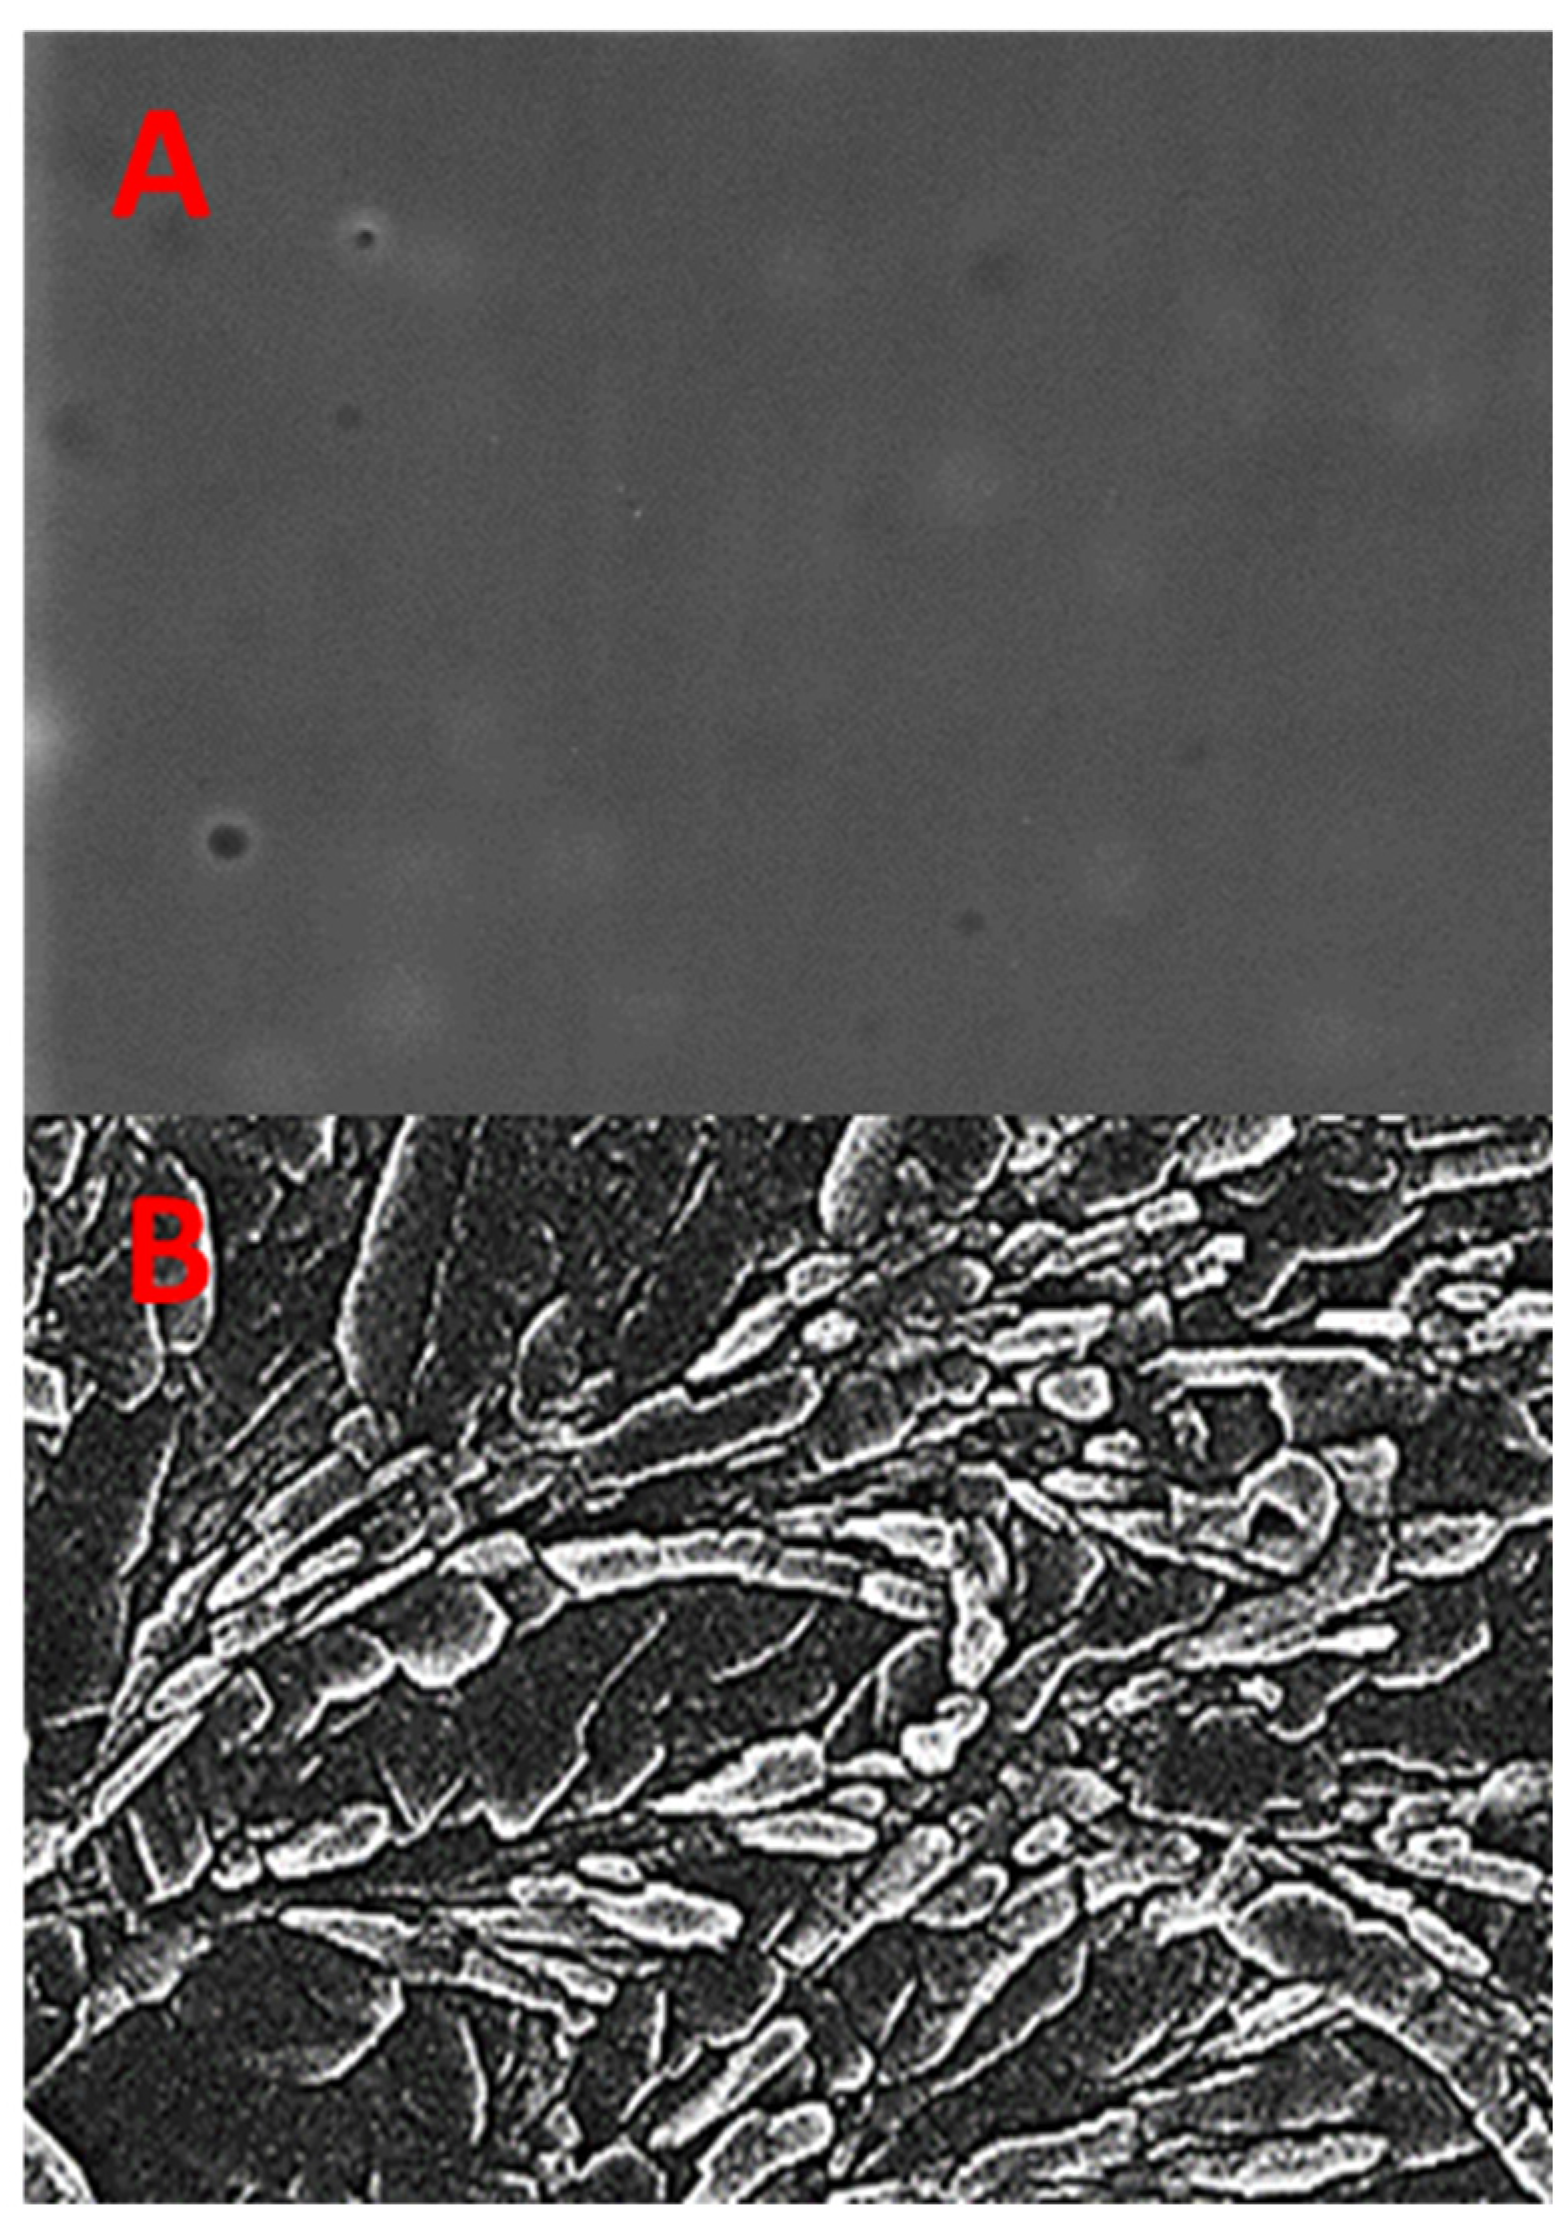

2.3. Scanning Electron Microscopy (SEM) of EHBR–ITHC Buccal Films